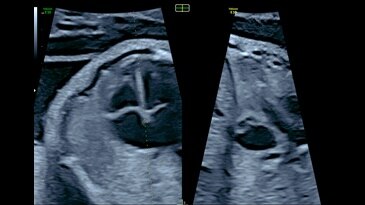

View of intraventricular septum with e4D Bi-plane imaging

13-week fetal profile